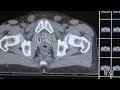

curiethérapie bas débit